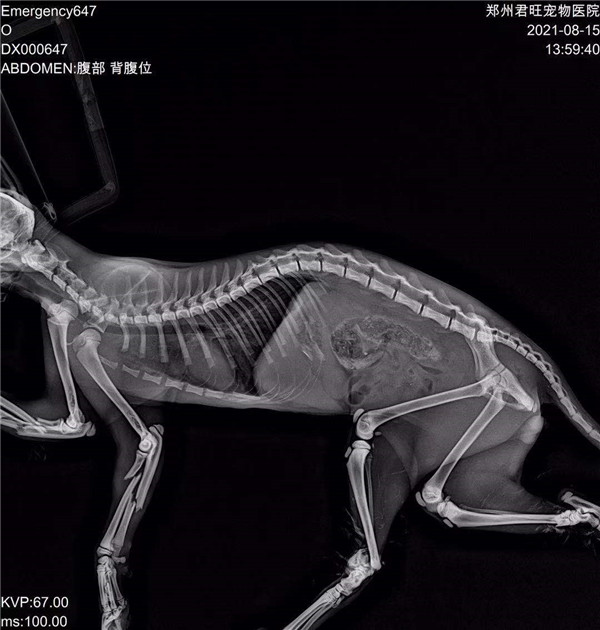

郑州市君旺宠物医院的翟医生,望着眼前面目全非的九福,微微锁起了眉头,简单检查过之后,就得出了判断:九福是被人虐待了。因为它的四条腿均是对称性骨折,两只前腿更是粉碎性骨折,满口牙也被拔掉了。“这绝对不是车祸,或者动物撕咬造成的,只能是人。”

被人折断四条腿、拔掉满嘴牙的“九福”的X光片。 本文图片 猛犸新闻